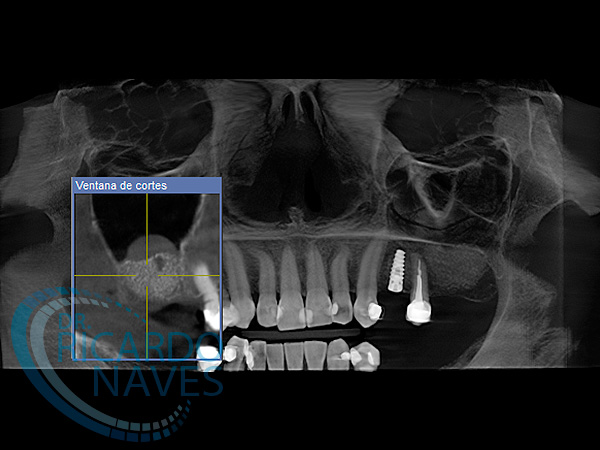

Elevación de seno maxilar técnica de ventana lateral.

Antes y después de elevación de seno bilateral. 5 meses de evolución. Obsérvese la cantidad de hueso que podemos ganar  en estas verdaderas cajas biológicas.